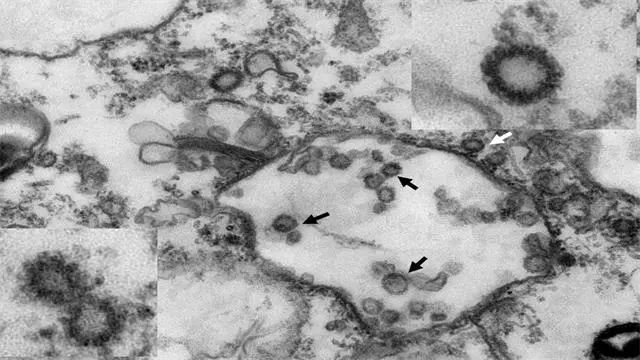

新型冠状病毒属于β属的新型冠状病毒,有包膜,颗粒呈圆形或椭圆形,常为多形性,直径60~140nm。其基因特征与SARSr-CoV和MERSr-CoV有明显区别。目前研究显示与蝙蝠SARS样冠状病毒(bat-SL-CoVZC45)同源性达85%以上。

从穿山甲分离的新型冠状病毒电镜照片 华南农业大学供图

在2月7日的发布会上,华南农业大学校长刘雅红介绍称,通过分析1000多份宏基因组样品,锁定穿山甲为新型冠状病毒的潜在中间宿主;继而通过分子生物学检测,揭示穿山甲中β冠状病毒的阳性率为70%;进一步对病毒进行分离鉴定,电镜下观察到典型的冠状病毒颗粒结构;最后通过对病毒的基因组分析,发现分离的病毒株与目前感染人的毒株序列相似度高达99%,以上结果表明穿山甲为新型冠状病毒的潜在中间宿主。研究结果对本次疫情的源头防控具有重大意义,也对野生动物管控的相关政策调整提供科学依据。